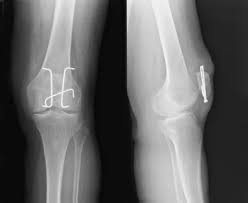

Löcher im knochen nach metallentfernung. Die ist hart und sehr spitz und lässt sich nicht bewegen. Obwohl ein Schraubenloch noch lange im Röntgenbild nachweisbar ist kommt es zu einer fortschreitenden Geflechtknochenbildung die die Stresskonzentration im Schraubenloch zunehmend herabsetzt. Bei Knie-OPs wird die Metallentfernung in der Regel cirka nach einem Jahr durchgeführt.

Immerhin wird das Bein bin zum Knochen geöffnet Gewebe und Muskeln durchtrennt und es verbleiben Löcher in den Knochen. Die Schraube im Schenkelhals ließ sich noch lösen die zwei Verriegelungsschrauben jedoch nicht - die Schraubenköpfe brachen ab die Gewinde wurden überbohrt und brachen wieder ab. Da die Drähte bei auch nur leichter Lockerung eine Gefahr für Strecksehen darstellen gibt es sehr gute Gründe die Kirschnerdrähte zu entfernen.

Obwohl sehr selten kann es im Rahmen der Metallentfernung ua. Nein dies ist ein völlig normaler Befund.

Gelegentlich ist es nicht möglich das Material vollständig zu entfernen so dass es auch vorkommen kann dass Reste des Metalls im Körper belassen werden müssen. Ich habe neulich das Gleiche bei einem Schrank erlebt. Die Stabilität sollte nach der Entfernung kein Problem sein weil die Schrauben und Nägel immer versetzt angeordet sind also die Löcher nie über- untereinander lägen. Die ist hart und sehr spitz und lässt sich nicht bewegen. Sollten Metallteile weggebrochen sein werden die dann auch im Knochen belassen die tun nix. Hier ist die Radiusfraktur nicht mit einer Platte sondern mit Kirschnerdrähten erfolgt. Obwohl ein Schraubenloch noch lange im Röntgenbild nachweisbar ist kommt es zu einer fortschreitenden Geflechtknochenbildung die die Stresskonzentration im Schraubenloch zunehmend herabsetzt. Hierbei wird in manchen Fällen lediglich die einzelne Stellschraube entfernt wobei die komplette Metallentfernung ungefähr nach einem Jahr beginnt. Auch nach einem Jahr kann man im Röntgenbild nach einer Schraubenentfernung die Schraubenkanäle gut erkennen.